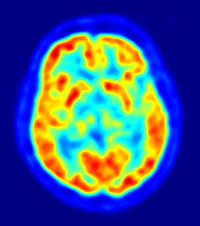

PET scan (positron emission tomography)

A visual display of brain activity that detects where a radioactive form of glucose goes while the brain performs a given task.